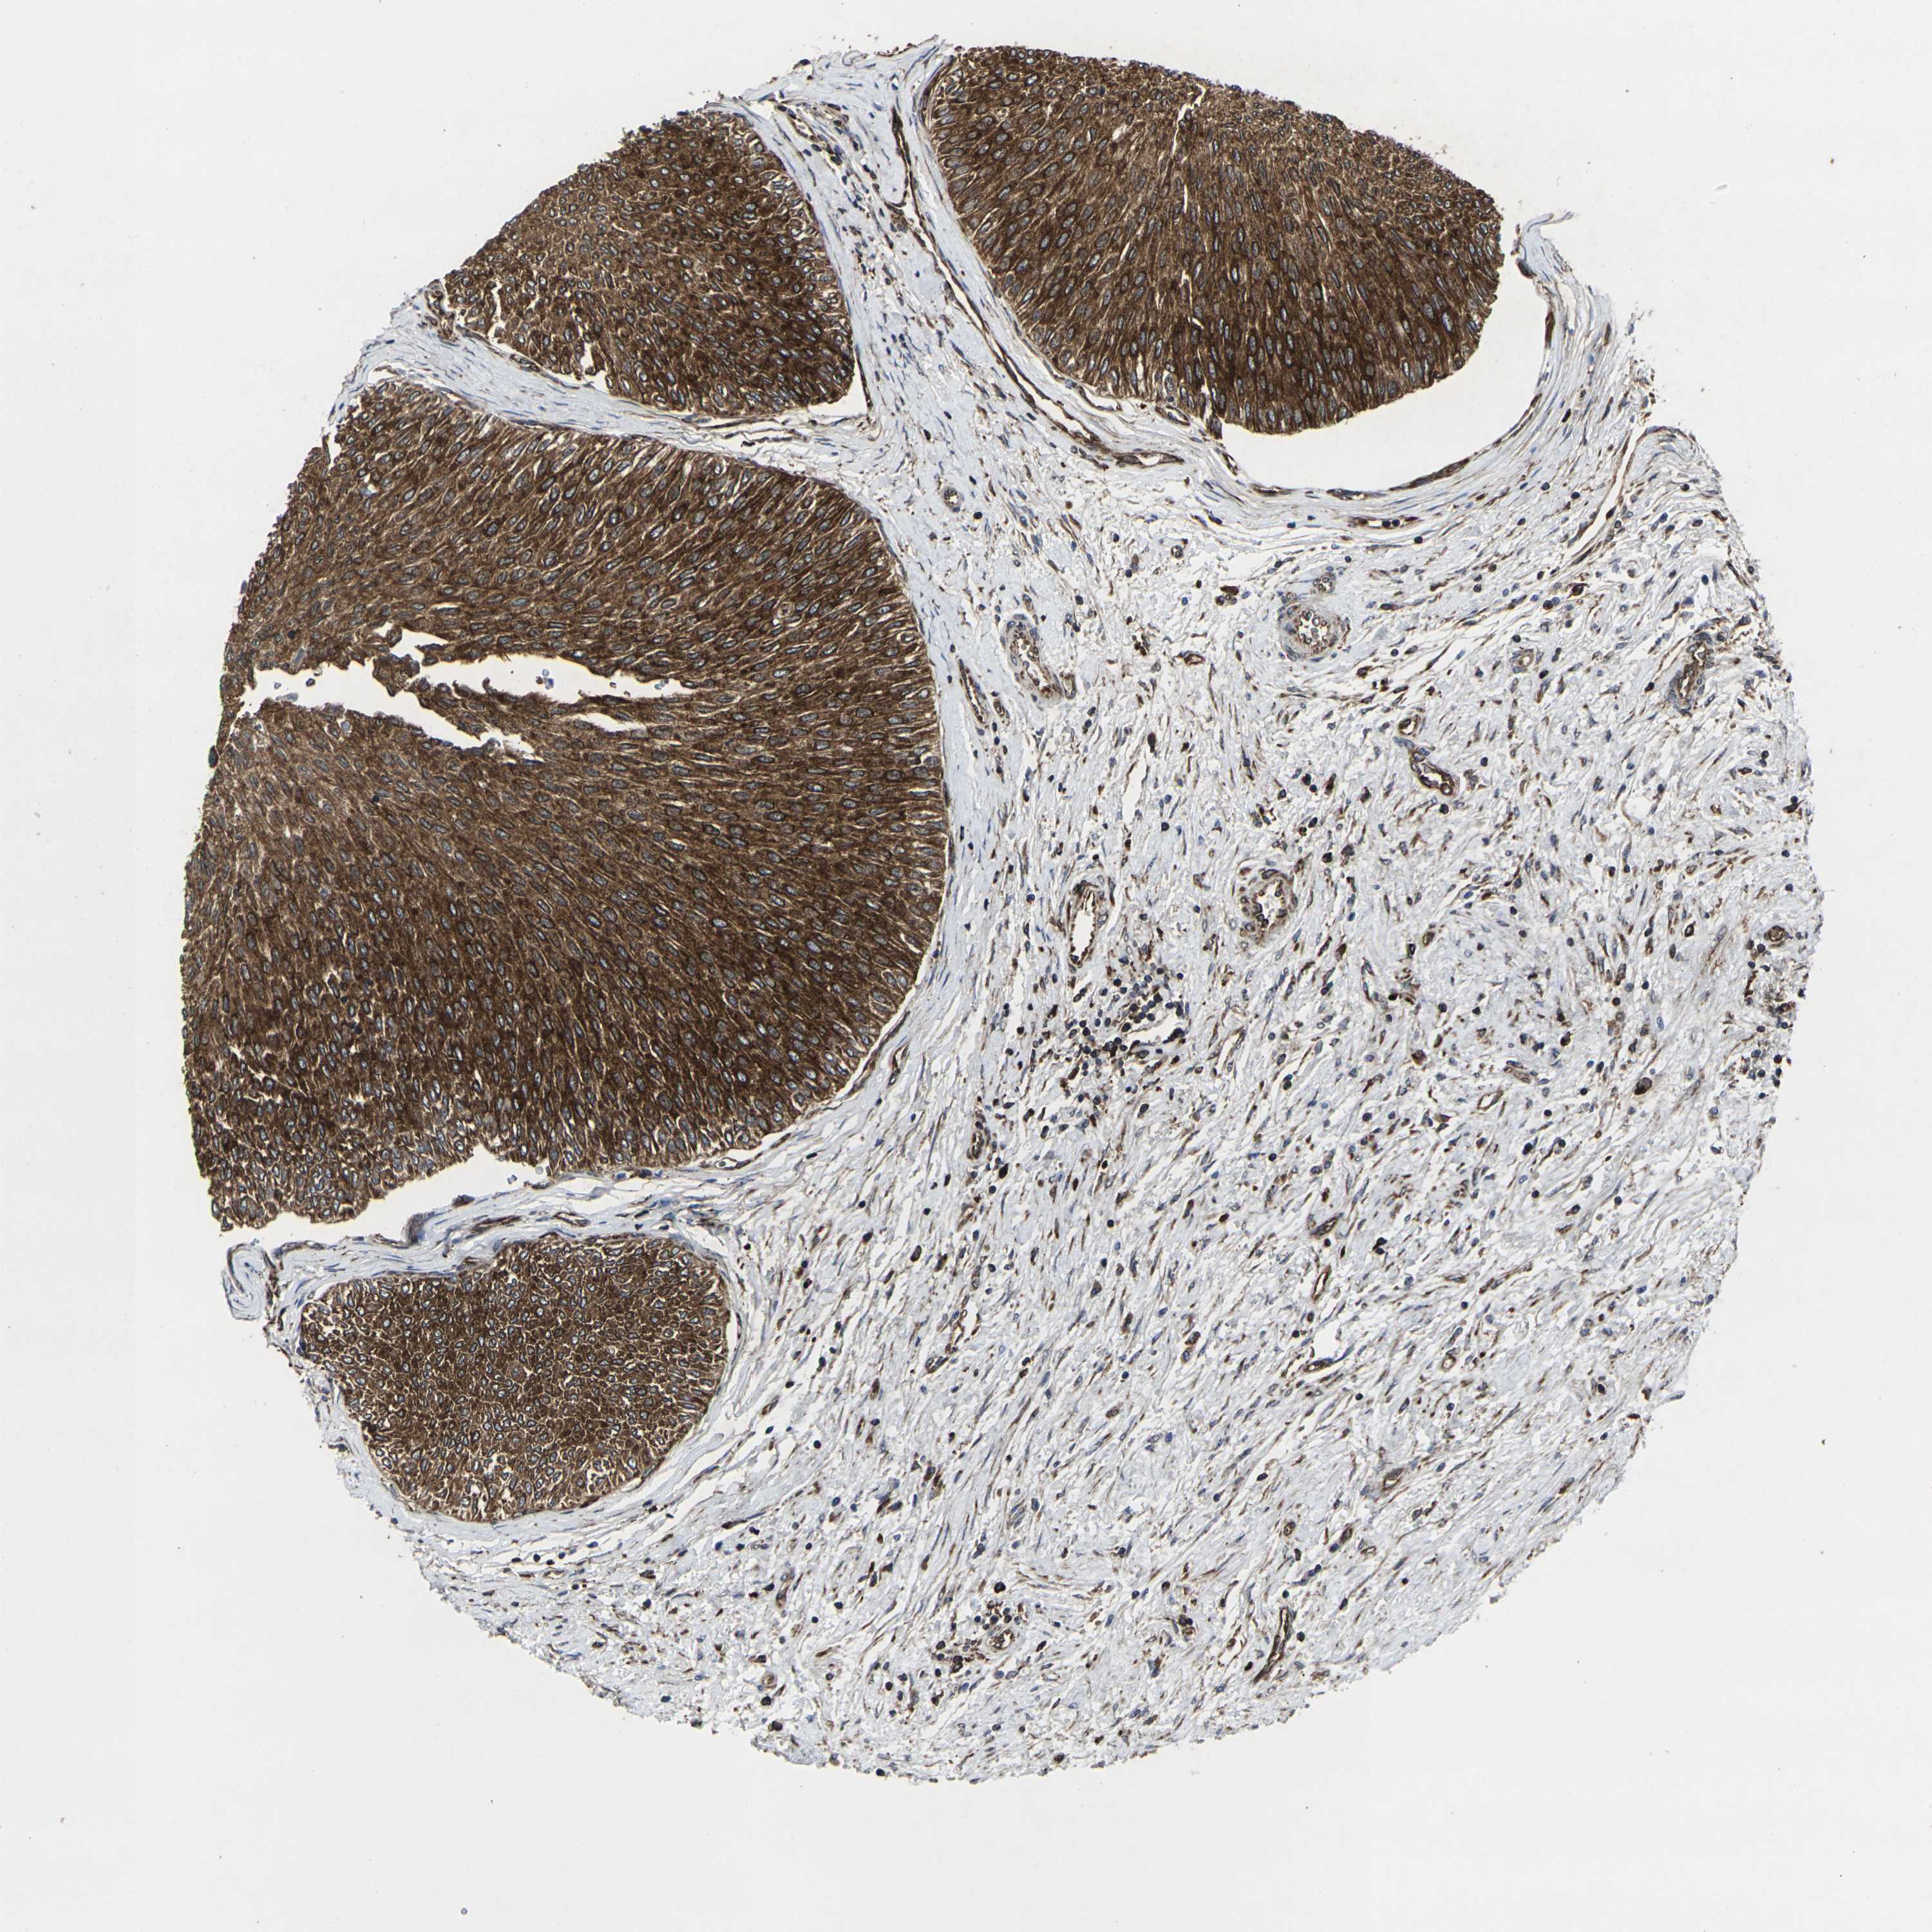

UROTHELIAL CANCER - Protein expressioni

A mouse-over function shows sample information and annotation data. Click on an image to view it in a full screen mode. Samples can be filtered based on level of antibody staining by selecting one or several of the following categories: high, medium, low and not detected. The assay and annotation is described here.

Note that samples used for immunohistochemistry by the Human Protein Atlas do not correspond to samples in the TCGA dataset.

Antibody stainingi

Antibody staining in the annotated cell types in the current human tissue is reported as not detected, low, medium, or high, based on conventional immunohistochemistry profiling in selected tissues. This score is based on the combination of the staining intensity and fraction of stained cells.

Each image is clickable and will lead to virtual microscopy that enables deeper exploration of all samples and also displays staining intensity scores, fraction scores and subcellular localization as well as patient and tissue information for each sample.

Antibody HPA014063

Staining

High

Medium

Low

Not detected

Intensity

Strong

Moderate

Weak

Negative

Quantity

>75%

75%-25%

<25%

None

Location

Nuclear

Cytoplasmic/membranous

Cytoplasmic/membranous,nuclear

Urothelial carcinoma, Low grade

Urothelial carcinoma, High grade